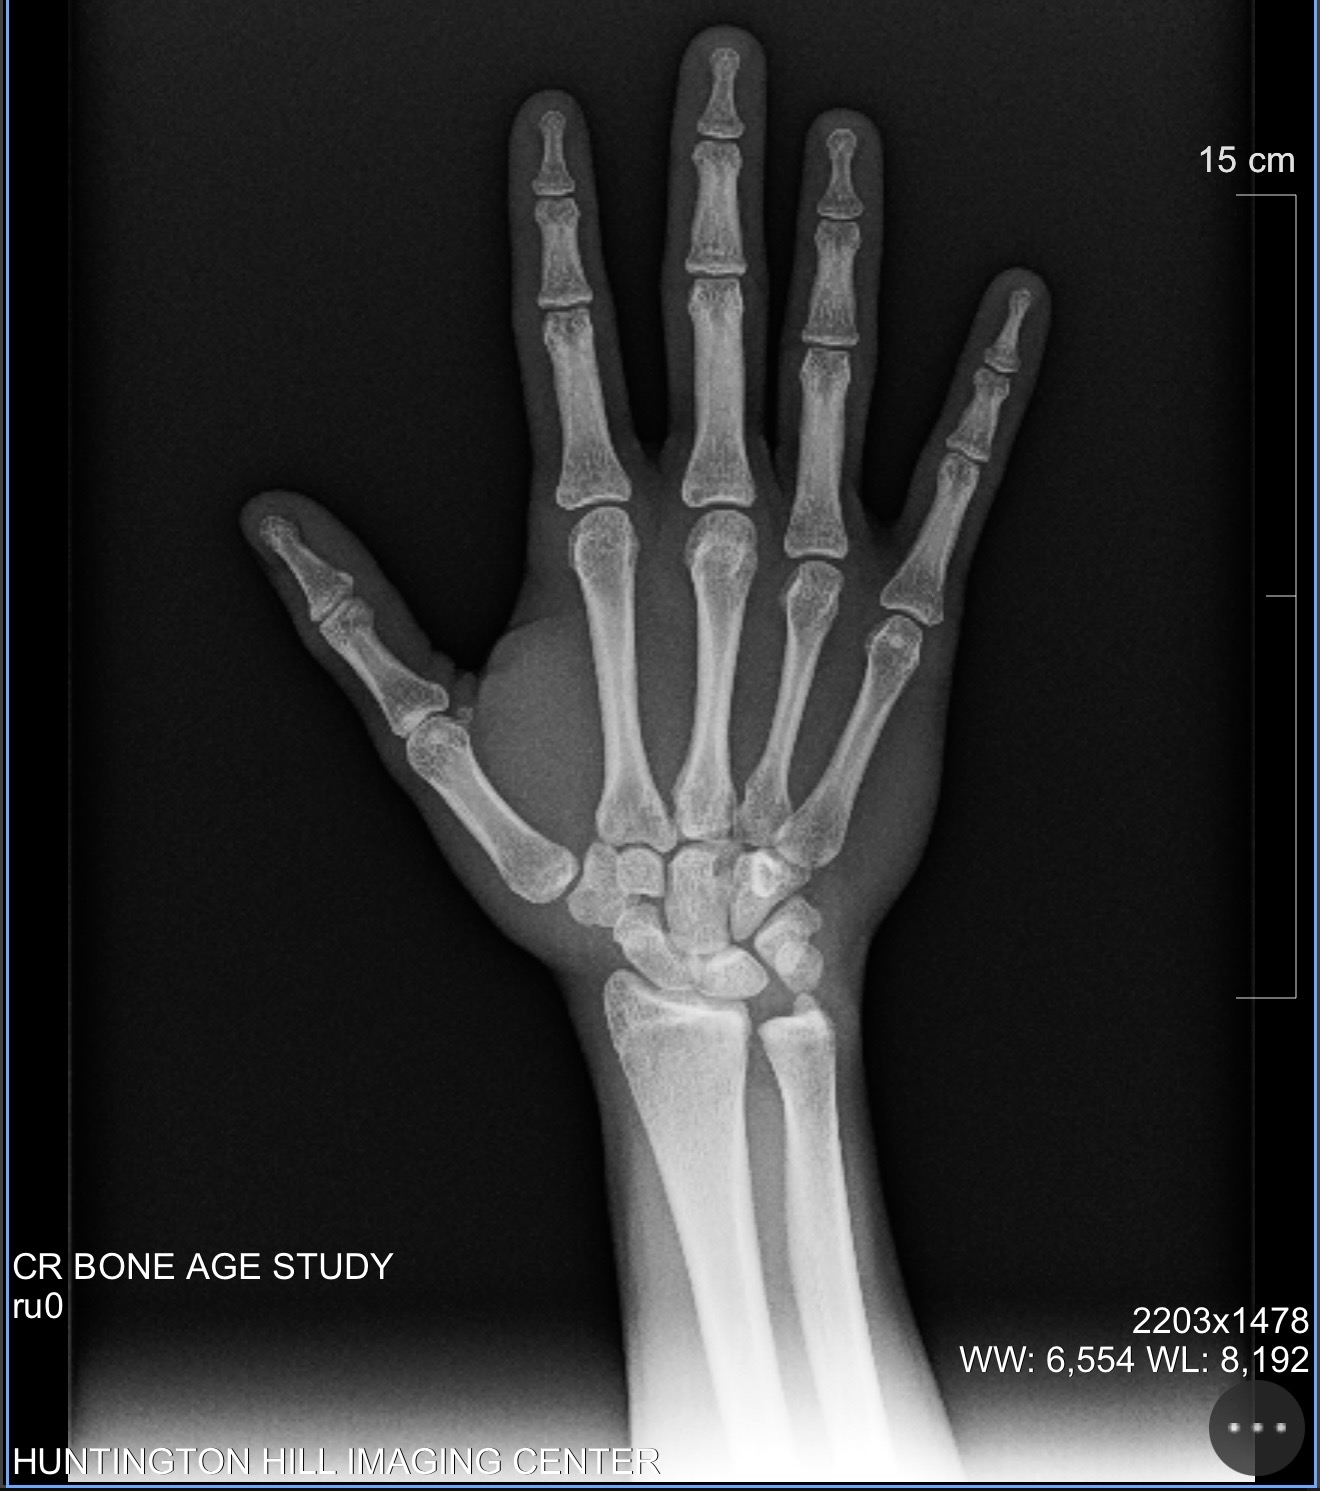

nah manI just got a bone scan yesterday and my growth plates are basically fused. Would hoping on hgh + ai or just hgh before they fully fuse be beneficial or should I just accept my fateš«©

I had rly high e2 for a while bc I decided to āexperimentā with things like rad140Cooked, how do peopleās plates close at 16![]()